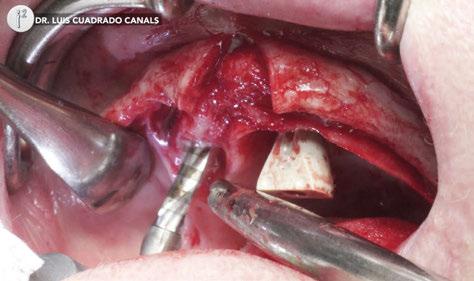

–Implante inmediato en incisivo lateral superior con técnica de «Socket Shield» y acceso vestibular para legrado de la lesión periapical, por el Dr. Ignacio Tormo Jiménez y cols. [106]

Protocolo Di2gitalArch® 2.0: Carga inmediata en el día en maxilar superior atrófico. Con Ziacom Galaxy, por el Dr. Luis Cuadrado Canals.